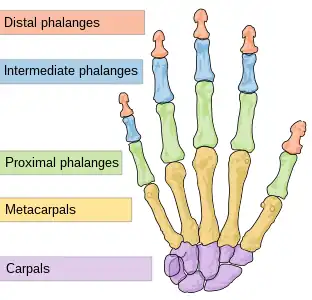

The bones in the hand

The bones in the hand The carpal and metacarpal bones in the hand